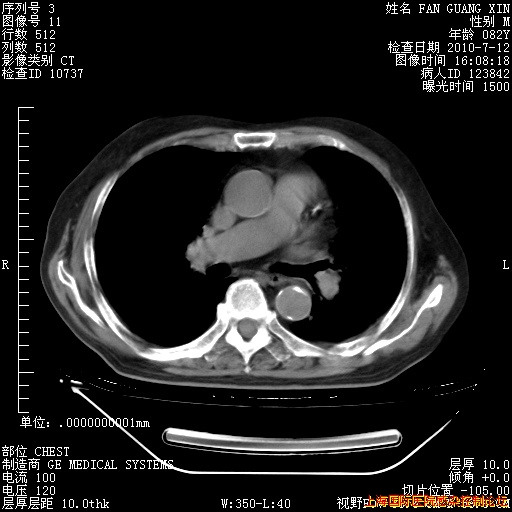

6月12日纵膈窗

今天复查CT

今天CT

整整相隔30天的肺部CT好像有所好转啊。甲强龙减量第3天,需要观察体温。

海管,自昨日你和我通完话后,不知您岳父消化道症状有无缓解?体温怎样?阅读7.12日胸部ct,个人认为目前激素治疗是有效的,甲强龙减量是适宜的。因在抗痨治疗,需密切观察肝功、肾功能和血常规。不过,老年、长期住院和大量使用激素,很担心菌群失调发生